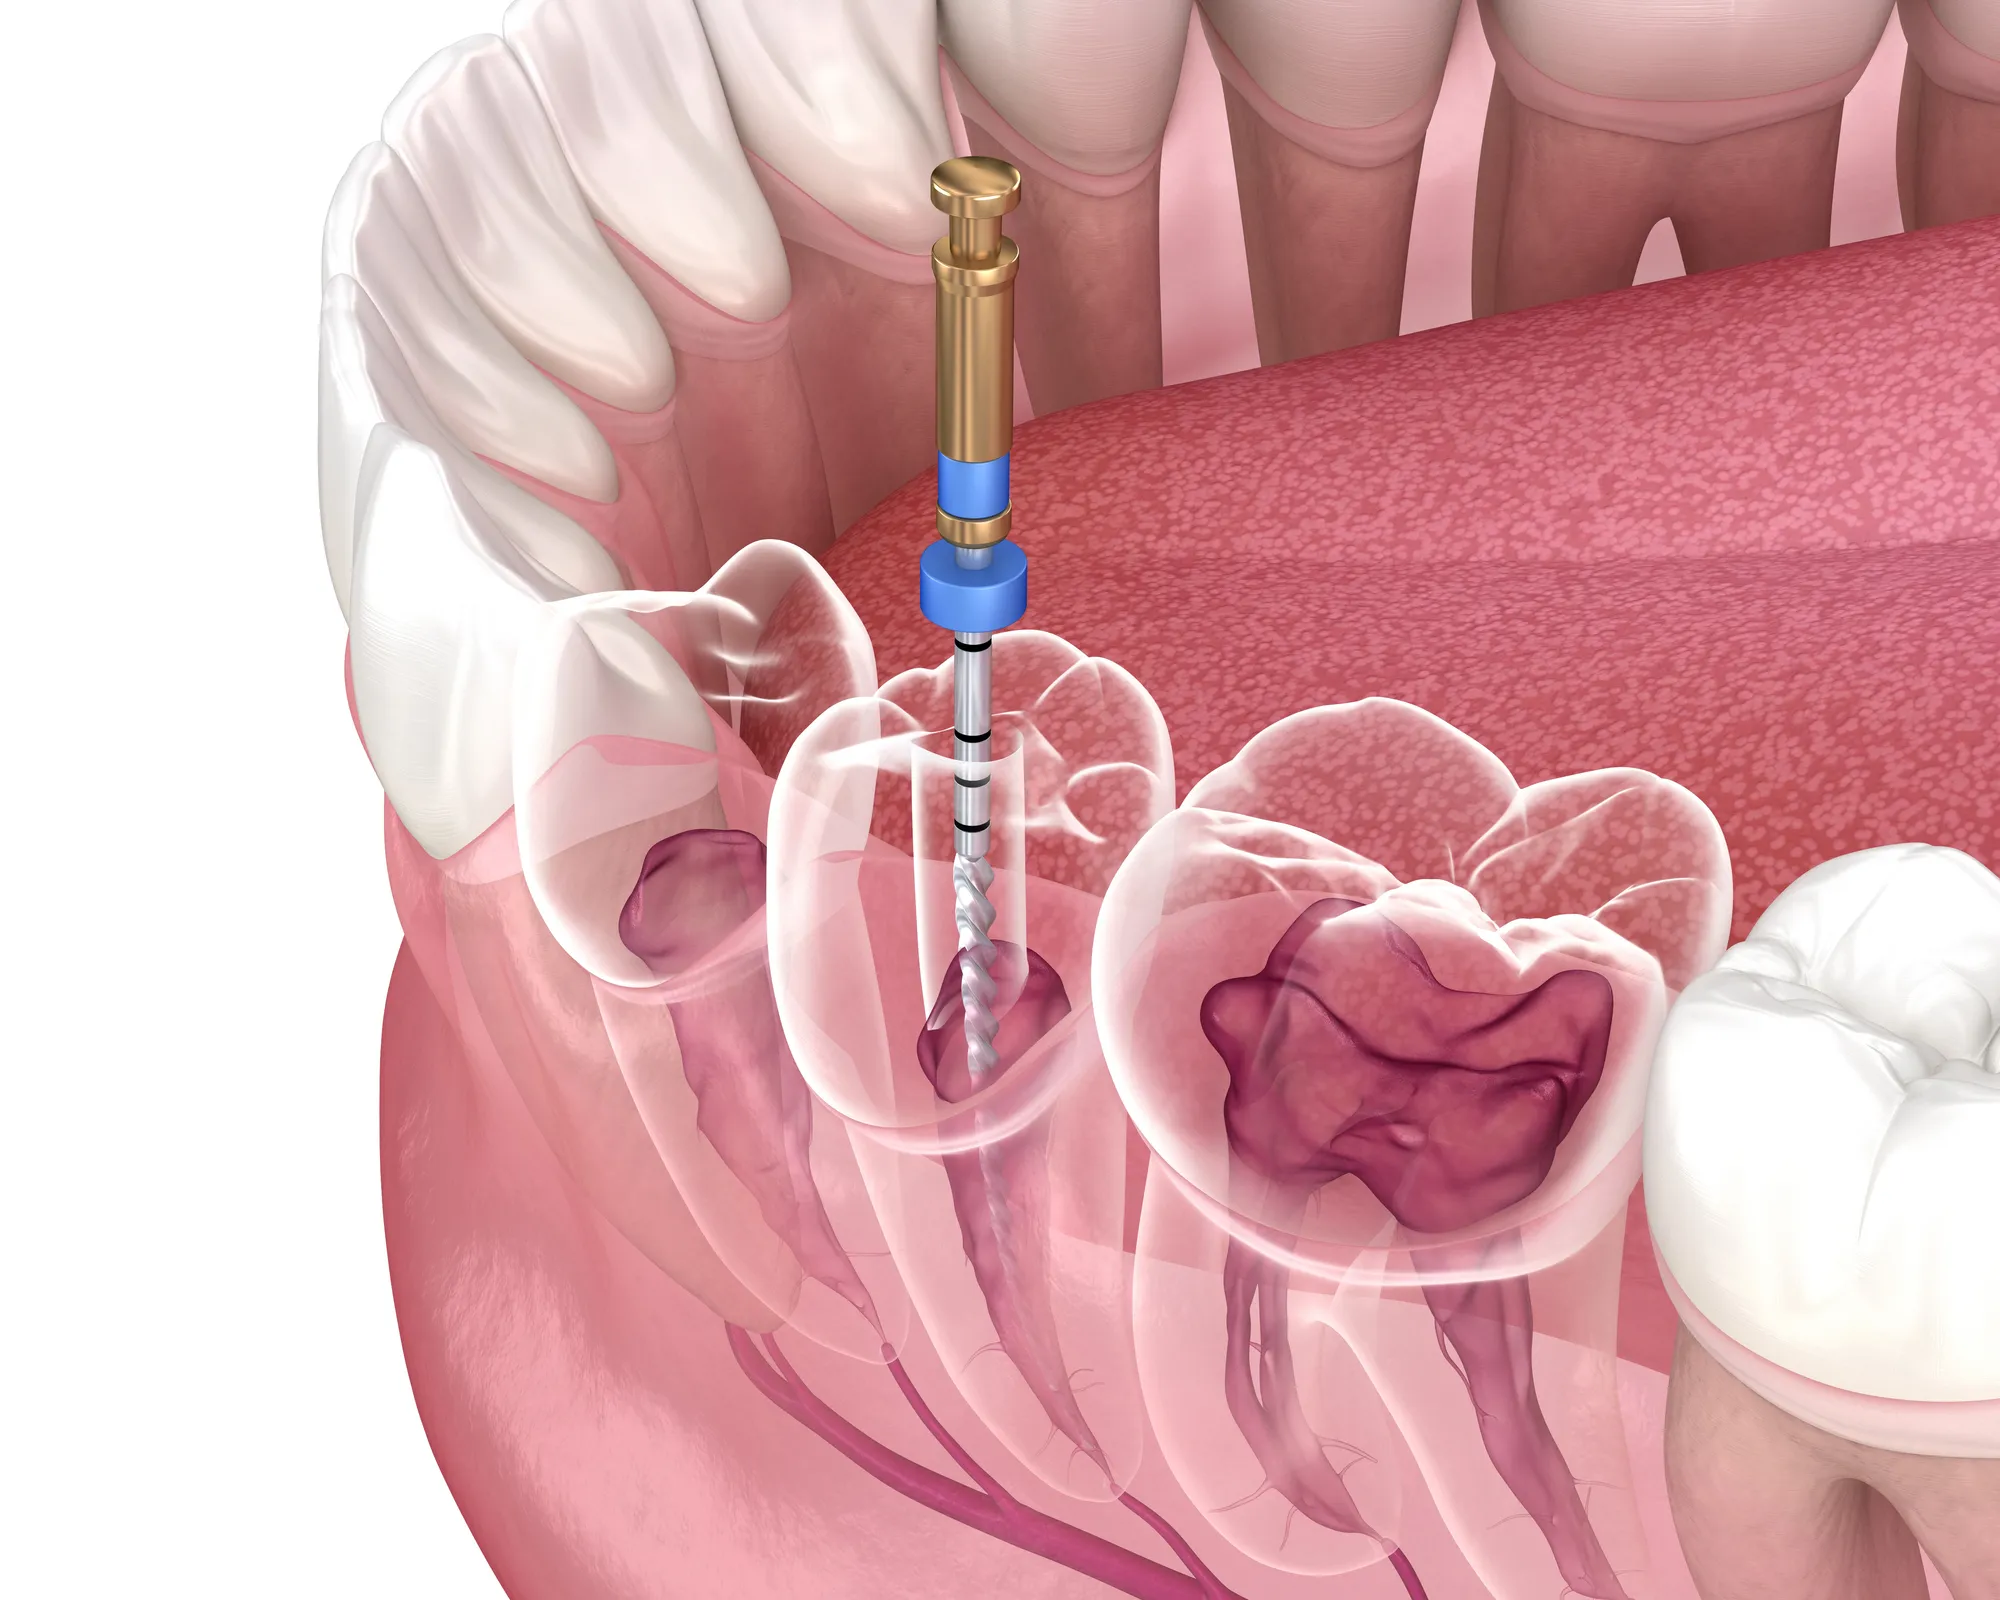

Root canal therapy, or endodontic treatment, focuses on the inside of your tooth, specifically the pulp, where nerves and blood vessels reside. When this area becomes infected or damaged, removing the infected tissue and sealing the tooth stops the spread of infection and relieves pain.

During the procedure, your dentist:

- Numbs the area with local anesthesia for a comfortable experience

- Removes infected or damaged pulp from the tooth’s root canals

- Cleans and shapes the canals to prevent further infection

- Fills and seals the canals to restore the tooth’s structure

- Places a dental crown, if needed, to strengthen and protect your tooth